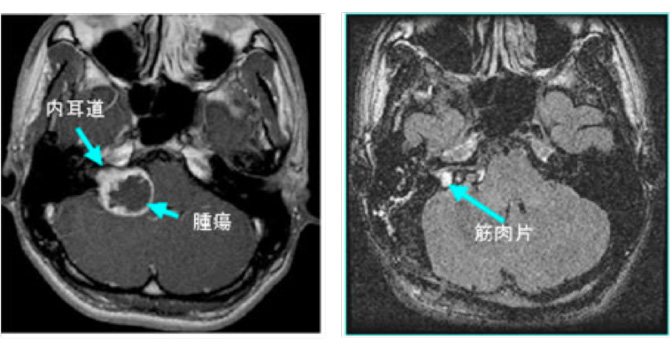

図1:20代男性 聴神経腫瘍

(左図)術前MRI:術前聴力は10dB

(右図)術後MRI:内耳道に筋肉片がおかれている術後聴力は温存16dB 顔面麻痺はなし

また高齢者でも手術は有益です。図2の症例は80歳の男性症例ですが、10年来右耳難聴で聴神経腫瘍の診断はつけられておりましたが、治療希望せず放置されておりました。しかし歩行障害が進行し当院に紹介されてまいりました。

造影MRIでは大型の腫瘍を認め、周囲の脳幹や小脳が強く圧迫され腫れています。手術にて90%の腫瘍摘出を行い、脳の圧迫もとれ、症状も改善し、治療後3年たった現在でも元気で外来に通っていらっしゃいます。

図2:80歳男性 歩行障害をきたした大型神経鞘種

(左図)治療前MRI:顕著な脳の圧迫と脳浮腫を認める

(左図)術後2年後のMRI:薄い残存腫瘍をみとめるが再増大なく、脳の圧迫は改善している